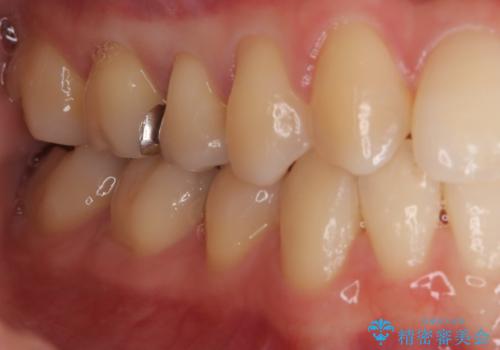

- 「銀歯を白しくしたい」を主訴に来院された患者さんです。

銀歯を外し、虫歯を除去した後にハイブリッドインレーで治療を行いました。

ハイブリッドインレーはセラミックと合成樹脂が混ざったものです。従って経年劣化や色の変化はあるものの、保険適応の被せ物に比べ、セラミックの含有率が高く、型取りの材料もシリコン材料を使用出来るので適合も優れています。